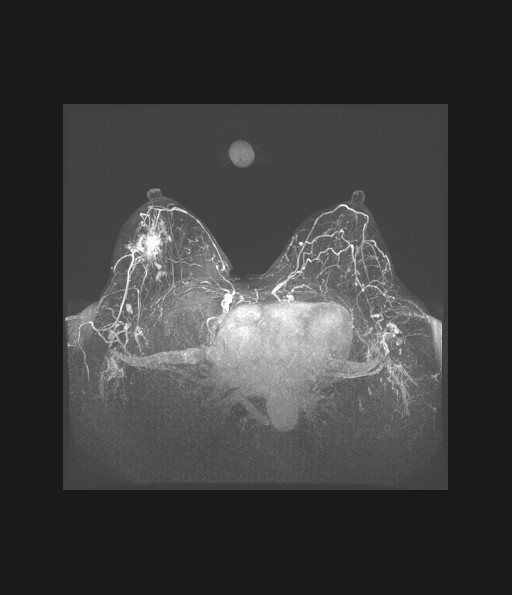

近日我院收治了一名55岁的女性患者,患者既往身体健康,于外院体检彩超及钼靶发现左侧乳房有一枚肿物,外院告知患者定期复查即可,此次患者来我院进行咨询后,考虑到彩超及钼靶对左乳肿物评分为“4a”类结节(恶性可能为2%-10%),抱着谨慎的态度,我院医生按照诊治规范为患者进一步完善了乳腺磁共振检查,结果发现患者除左乳结节外,在右乳存在隐匿性的新病灶,评分为“4b”(恶性可能性为10-50%),在与患者本人及家属进行了耐心的沟通与讲解后,我院乳甲外科对右侧病灶进行检测后证实右侧病灶为乳腺癌,并进一步为患者完成了乳腺癌的保乳手术,患者目前已康复出院。

乳腺癌是我国女性最常见的恶性肿瘤,我国现已将乳腺癌的筛查纳入国家重大公共卫生服务项目,彩超和钼靶是最常用的乳腺癌筛查手段,但早期乳腺癌的临床表现并不十分典型,彩超及钼靶结果正常时,患者不应该掉以轻心,应及时向临床医生进行咨询,必要时应完善乳腺磁共振排除可能存在的隐匿性病灶,以达到早发现、早诊断、早治疗的目的。磁共振相较于钼靶和彩超,其灵敏度和特异度更高,更容易乳腺中的隐匿病灶及多中心、多灶性病变,同时,对于乳腺癌高危人群,如彩超及钼靶结果为阴性,必要时需完善磁共振。